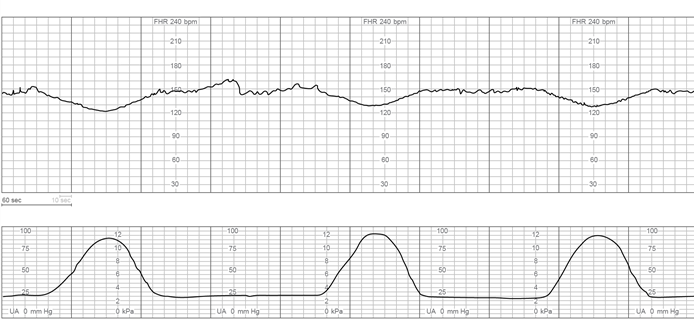

The charge nurse is observing fetal heart rate (FHR) tracings of 4 clients who have just been admitted to labor and delivery triage. Which FHR pattern would be most concerning to the nurse?

B)